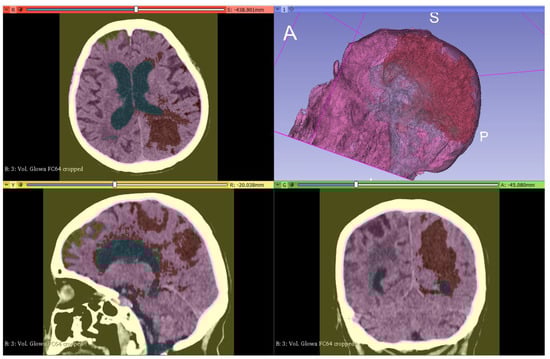

2.4.2. Segmentation

2.4.3. Model Creation and Visualization